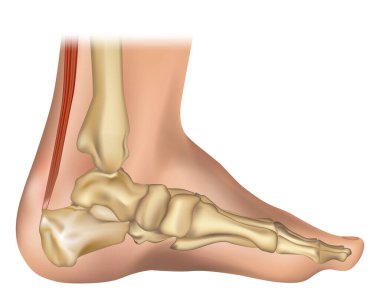

3 boyutlu Talus tarsal kemiği ve beyazı kopyalama alanı ile izole edilmiş. İnsan iskeleti, ayak ve ayak bileği anatomisi, tıbbi diyagram, osteoloji, iskelet sistemi kavramları.

RenkKırmızıbeyazArkaplanRenderGörünümrenkliresimlemeİzole edilmişkenarİnsanSağlıkİlaçSağlık hizmetleriTıbbisiluetBoşlukKemikgövdebiyolojiBilimprofilAyakSistemkemiklerEklemdoğrugörüntü oluşturmaİskeletanatomidiyagramlateraltalustarsusAyak bileğiözetlerkontüriskeletanatomikBoşluğu kopyalaKes şunuosteolojitarsalstarsalBenzer İçerikler